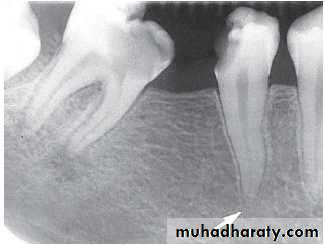

Periapical inflammatory lesions :

Is a local response of bone around apex of tooth that occurs 2° to pulpal necrosis or extensive periodontal disease..

Radiographic features:

Location: Apex of involved tooth / Cervically up the tooth root.Periphery: Ill defined / Well defined, with gradual blending of normal trabecular pattern into sclerotic pattern.

Internal structure: *Early lesion→ no radiographic change.

*Widening of PDL space at the apex.

*A mixture of sclerosis (radiopaque) and rarefaction (radiolucent).

* ↑se bone formation → periapical sclerosing osteitis.

*↑se bone resorption → periapical rarefying osteitis.

Effects on surrounding structures:

* Losing of lamina dura at the apex.* Regions of sclerotic bone around apex.

* External apical root resorption.

* Inflammatory periosteal reaction (new bone formation in max. S.) → halo shadow.